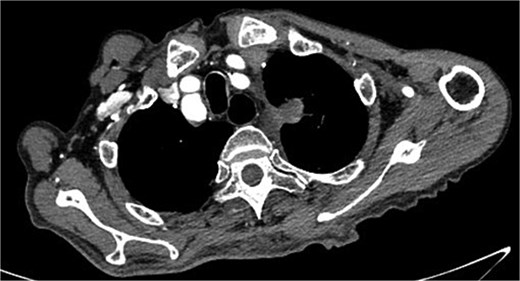

Despite recovery, the patient remained physically exhausted and required ongoing rehabilitation. In May 2023, after a COVID-19 infection, the patient experienced blood in phlegm. CTA confirmed successful aneurysm repair with no endoleak (Fig. 3). Thus the patient was hospitalized in the respiratory department. Relevant pulmonary examination indicators and lung CT results revealed no lung lesions associated with blood in sputum (Fig. 4). However, throughout July, 2023, intermittent blood in phlegm continued, and a CTA on July 19, 2023, revealed a type IV endoleak (Fig. 5). Conversely, aortography on July 27, 2023, showed no obvious endoleak. Closed drainage of the left thoracic cavity was performed, but blood in phlegm recurred on August 9, 2023. A Gore C-TAG stent graft was deployed in the thoracic aortic arch, with its proximal end anchored at the ostium of the left subclavian artery stent graft to ensure complete coverage of the endoleak site both proximally and distally(Fig. 6). Post-surgery, blood in phlegm symptoms abated.

Lung CT results revealed no lung lesions associated with blood in sputum.